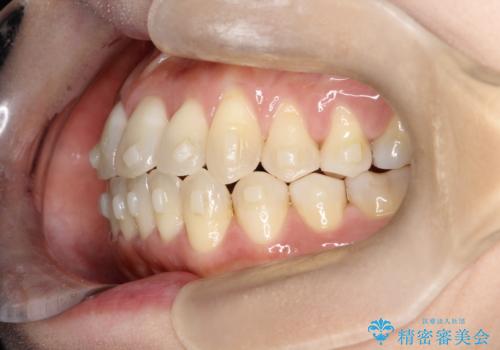

【開咬】笑った時の見た目を改善したい。

- 重度の開咬でしたがインビザラインで適切に治療計画を立て、きれいに仕上がりました。